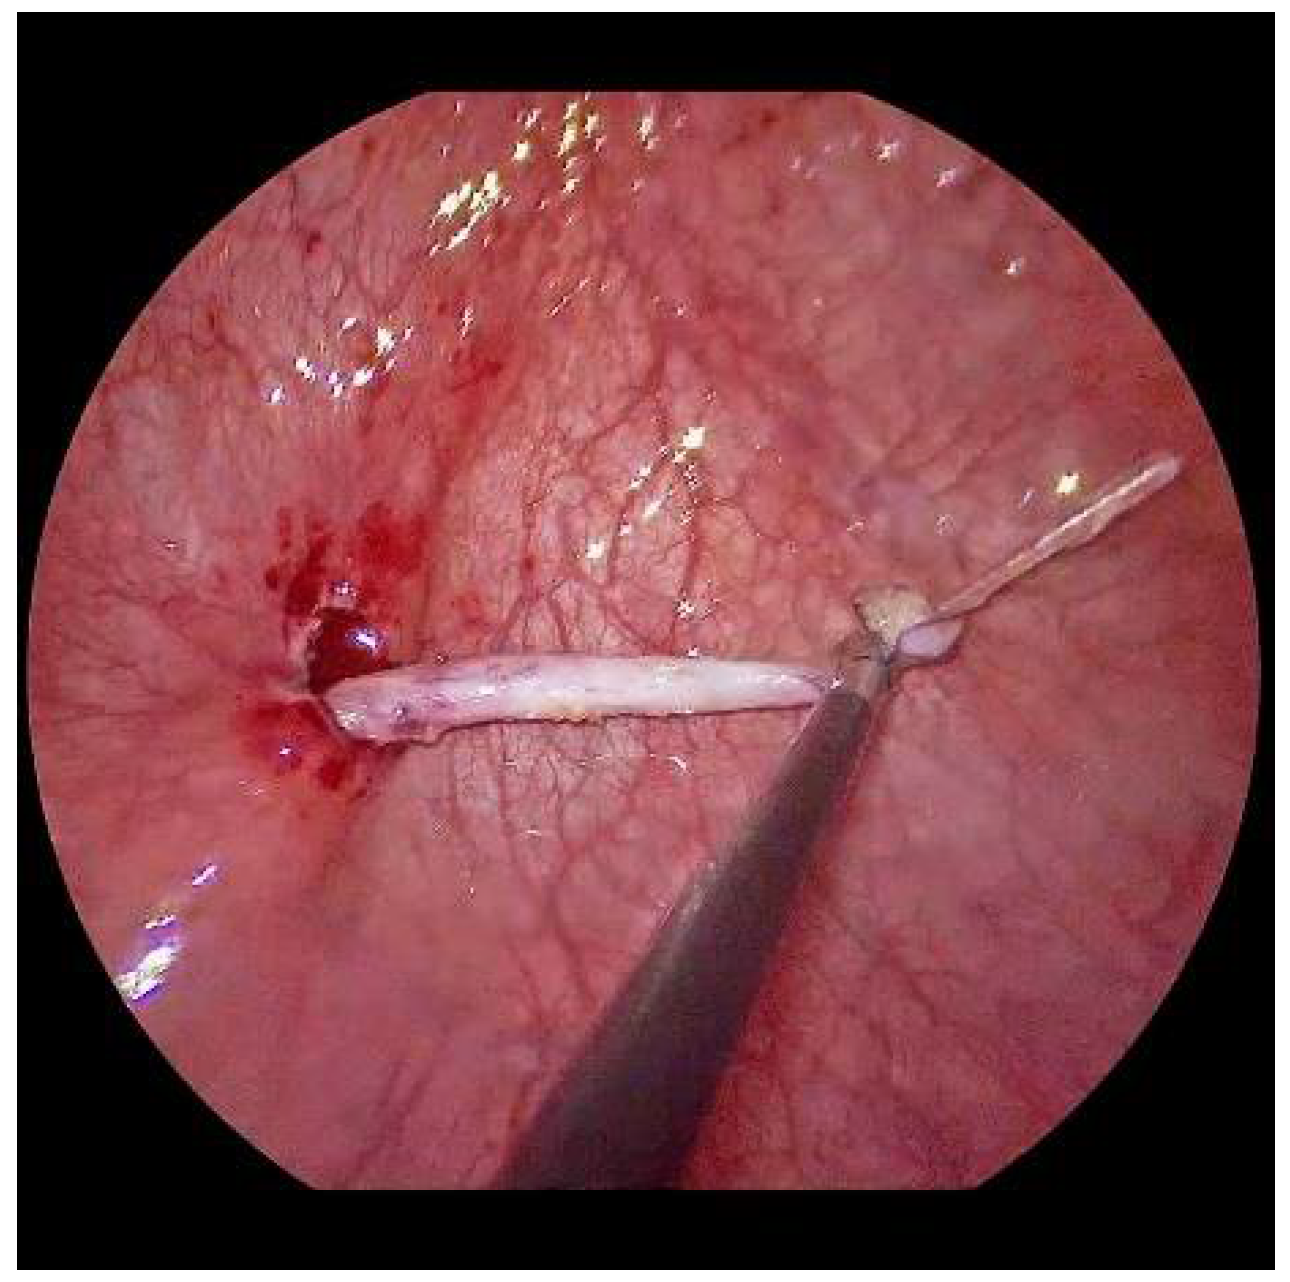

Now, the ureter is intubated with a 3 or 4 Fr. silicone tube, followed by subtle circumferential electrical mucosa incision with a fine dissecting needle (Figure 3). The ureteral release is continued using an electrical hook for at least 4 to 6 cm until it can be positioned without tension to the opposite ostium (Figure 4). Duplicate ureters are intubated twice and mobilized together. If bilateral, the submucosal tunnel is created between the two ostial incisions. If not, an additional mucosal incision is made 1 cm canially of the opposite regular ostium (Figure 5).

Figure 3. For a left-sided VCUR, the ostium is circumferentially incised with a fine needle while gently pulling on the intubated left ureter.